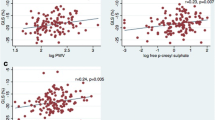

Patient characteristics are reported in Table 1. In patients with ICM, creatinine was associated with myocardial function as determined by GLS (r = 0.46, p < 0.001). These data remained consistent also with regards to both GCS (r = 0.34, p = 0.001) and GRS (r = − 0.40, p < 0.001), as presented in Fig. 2A–C. Similarly, urea showed a significant association with GLS (r = 0.34, p = 0.001), GCS (r = 0.30, p = 0.005) and GRS (r = − 0.31, p = 0.003), as shown in Fig. 2D–F. Concordantly, eGFR was significantly associated with GLS (r = − 0.40, p < 0.001), GCS (r = − 0.27, p = 0.012) and GRS (r = 0.34, p < 0.001) (Fig. 2G–I).

Creatinine, urea and eGFR are significantly associated with global myocardial strain in CMR. In patients with ICM, creatinine was significantly associated with GLS. These data were confirmed by both GCS as well as GRS (A–C). In addition to creatinine, urea (D–F) and eGFR (G–I) showed a significant association with GLS, GCS and GRS